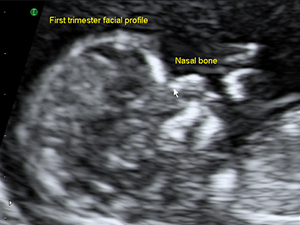

First Trimester